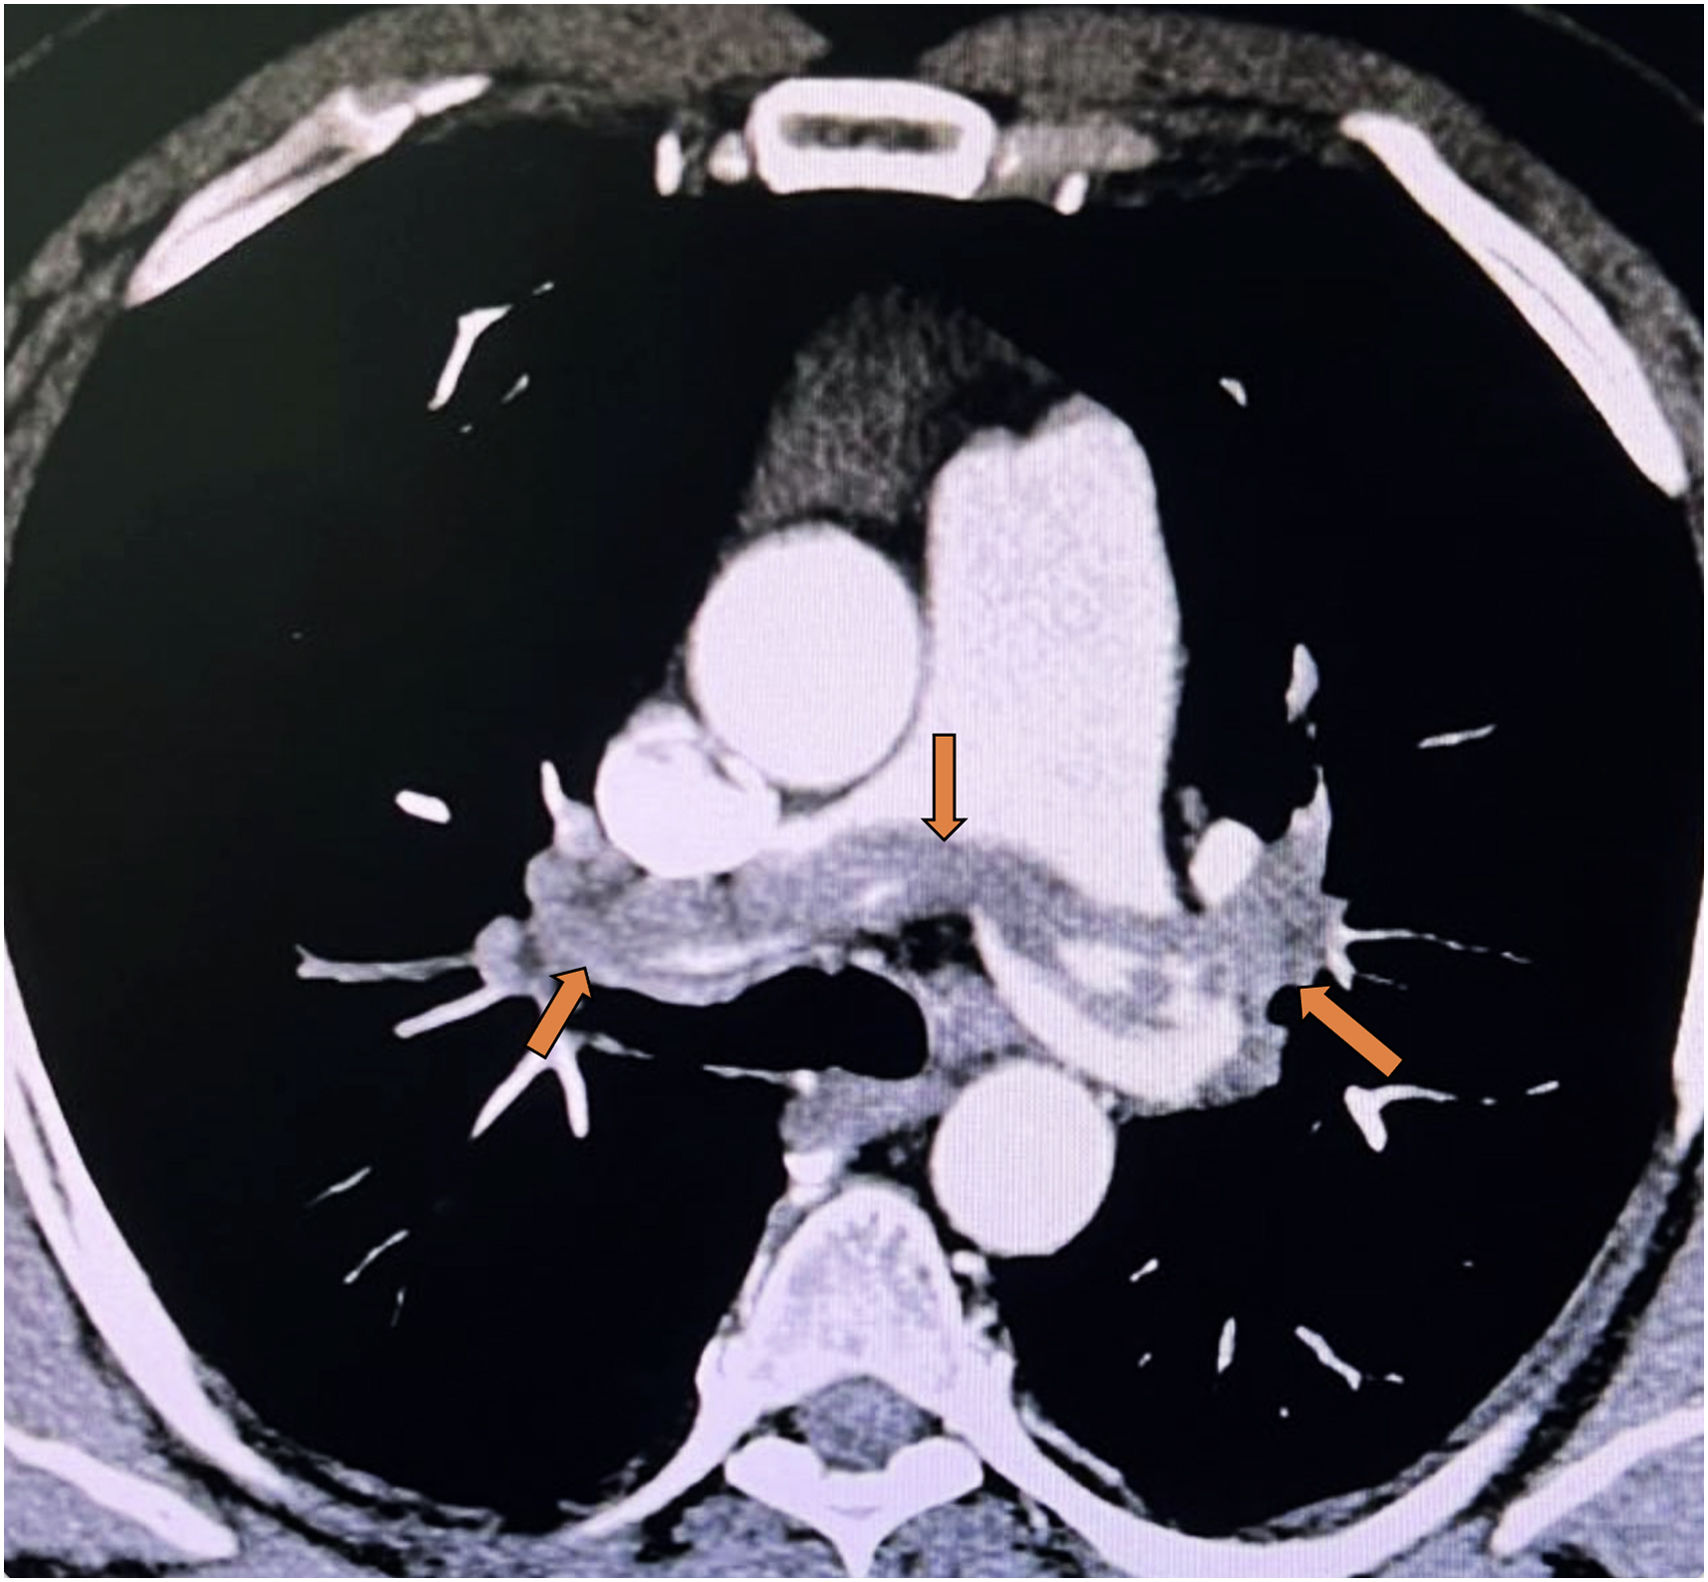

Saddle Pulmonary Embolism in Hemodynamically Stable Patients: Clinical Implications and Unresolved Questions